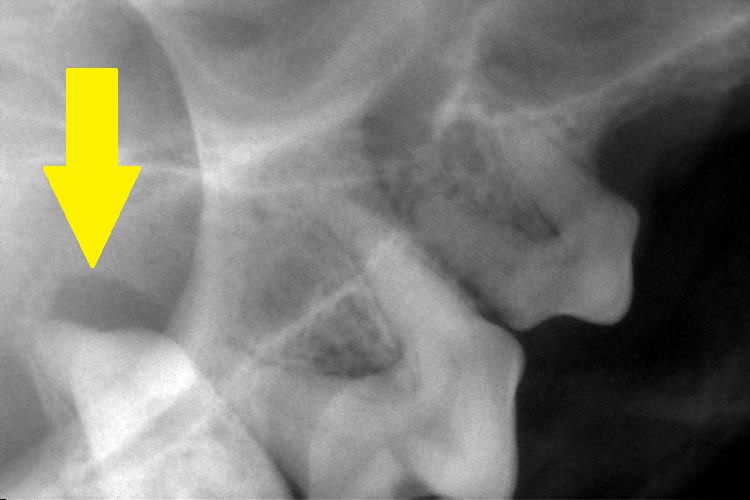

上顎の切歯はすべて歯根の周りが黒く抜け、歯を支えている部分がとても少ないことがわかります。

右上顎第1後臼歯は歯周ポケットが9㎜もありぐらついていたので、レントゲンで確認したところ、

この歯も歯根部が黒く抜けていました。

これらの歯は、歯周病の進行により歯を支えている歯槽骨が吸収され、ぐらついています。